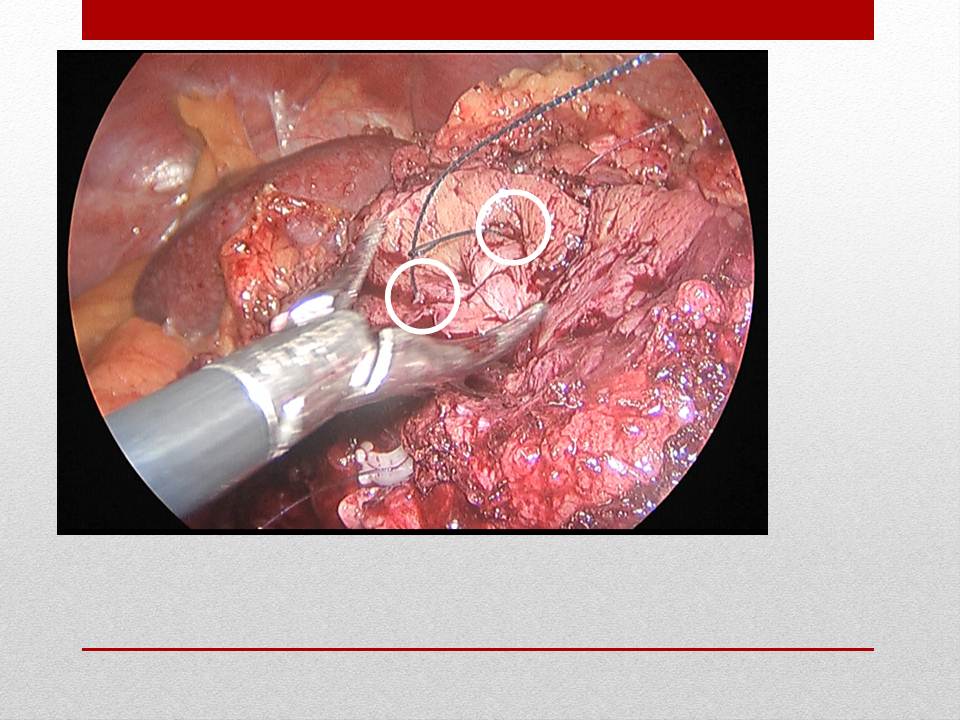

大家可以看一下这张图,显示的就是一个肠管的电灼伤,对于这样的损伤的话,给它扩大范围,做一个八字缝合,包埋一下,往往就是安全的了。